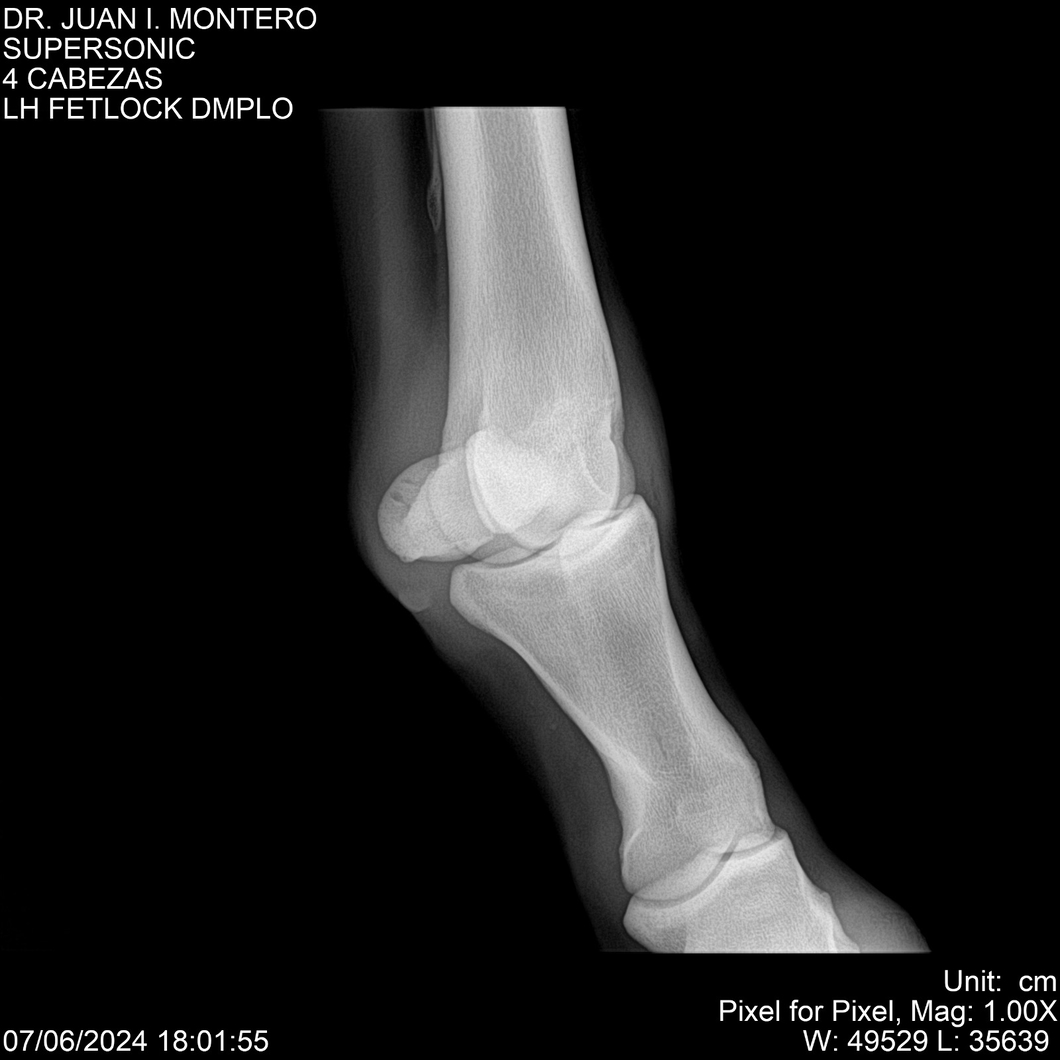

LOTE 5, SUPER SONIC Lote Anterior Volver al remate Lote Siguiente Ficha Contacto Montevideo - Ficha del Lote Identificador: #281089 Categoría: Yeguarizos Montevideo - 69 Visualizaciones ClicData Contacto Empresa: Abelenda N. R., Walter Hugo Nombre*: Teléfono* : E-mail* : Mensaje Enviar Registrese gratis Este contenido Exclusivo está disponible sólo para usuarios registrados Ingresar